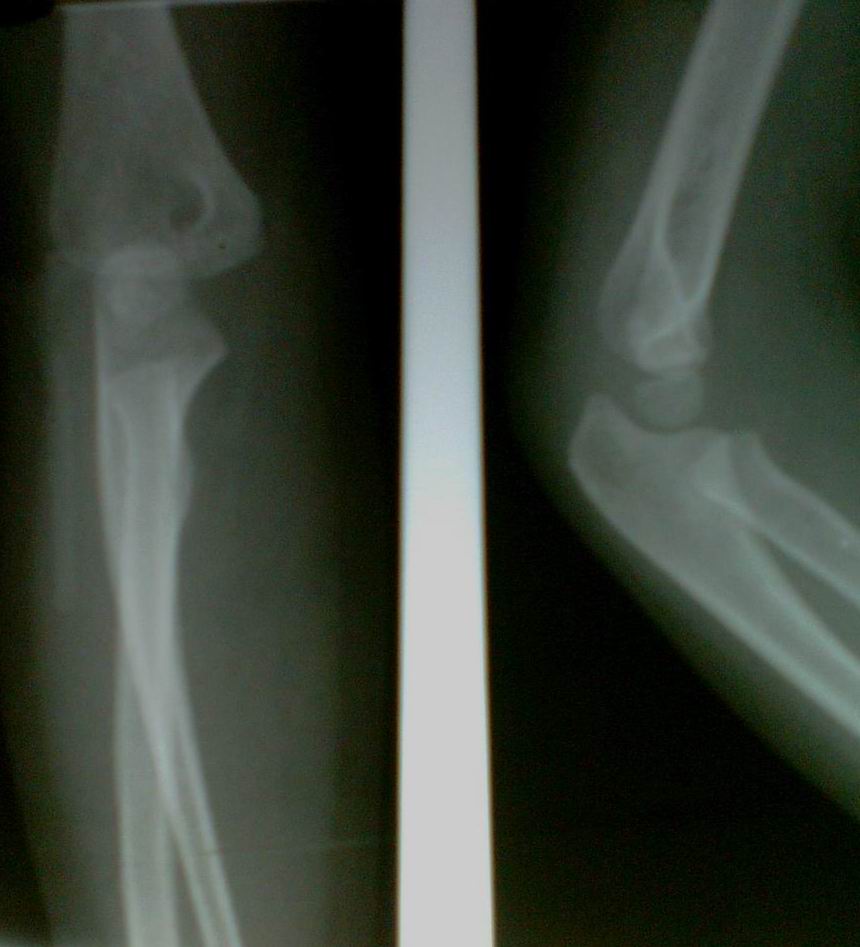

以下是引用余辉在2009-5-29 17:19:00的发言:[br]体位的问题,前臂没有旋后